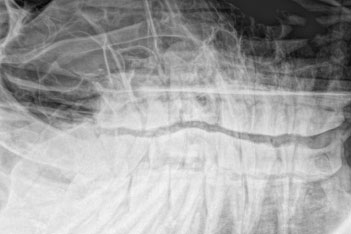

Ambulatory Service Emergency 24/7/365 Lameness & Sport Medicine Regenerative Therapies Surgery Diagnostic Imaging Internal Medicine Reproductive Center Dentistry Ophthamology Spinal Manipulation Acupuncture Podiatry Service Laboratory Barns and Paddocks